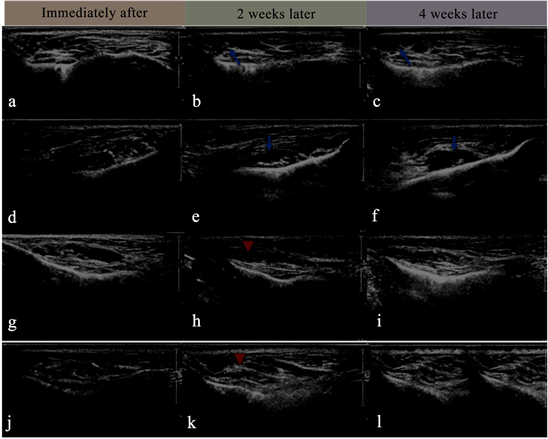

Follow-up HRU imaging at 2 and 4 weeks showed that hydration of the CHAP-HA would occur, and the CHAP-HA would appear to be more heterogenous and hyperechoic (Figure 5). In the majority of cases (13 of the 20 injections in 8 patients), the HA became completely unidentifiable with the surrounding

Figure 5. High-resolution ultrasound imaging immediately after HA injection (a, d, g, j), at 2-Week (d, e, h, k) and 4-week (c, f, i, 1) follow up. Hydration of the HA would occur (arrows), and the ha would appear to be more heterogenous and hyperechoic (arrowheads) and may became completely unidentifiable with the surrounding tissues in the 4th week follow up (i, j).

tissues at the 4th week follow-up (Figure 5(i) and Figure 5(l)).